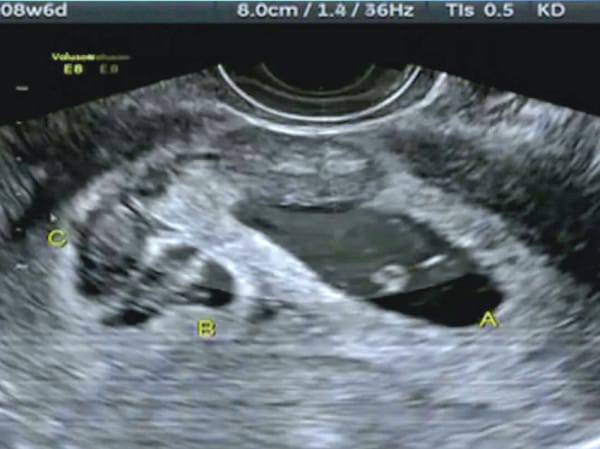

In gergo medico si chiama superfetazione ed è un fenomeno molto, molto raro. Si verifica quando, dopo la fecondazione di un ovulo e la formazione di un feto viene rilasciato un secondo ovulo che viene a sua volta fecondato.

Kate quindi è rimasta incinta della sua seconda bambina quando era già incinta di due gemellina, di cui una non è sopravvissuta.